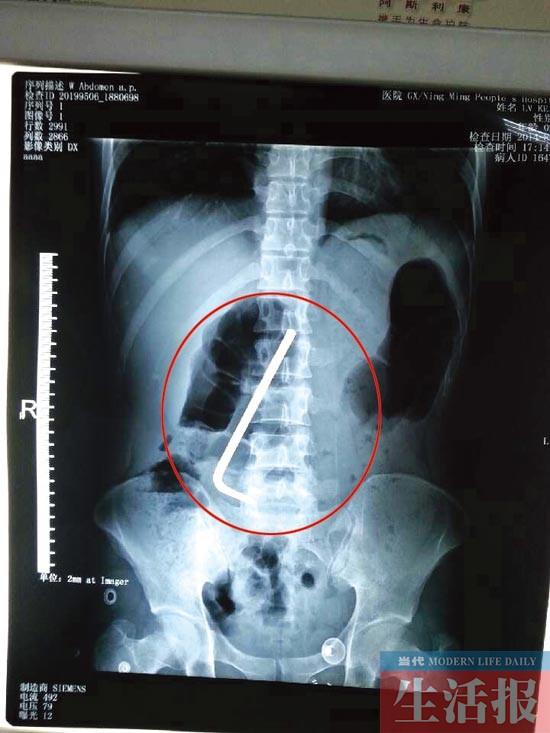

CT结果显示金属钩处于小强的十二指肠球部上

在自治区人民医院,小强的CT检查结果显示,其十二指肠球部上卡有一条长约13厘米的L形金属钩,医生确诊,这就是引起小强腹痛的罪魁祸首。